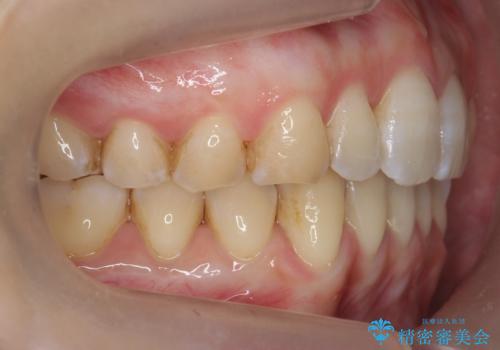

前歯のガタつき インビザラインで 下の前歯を1本抜歯

- 前歯のがたつきを主訴に来院。マウスピース矯正を希望されました。

治療にあたり、下の前歯を一本抜歯しています。

非抜歯で無理に治療をしようとすると、下の前歯の骨が薄く歯ぐきが下がったり、歯がぐらついたり、がたつきが完全にとれないリスクがあることを説明しました。

下の前歯が3本になるため、上下の正中は合わない仕上がりとなりますが、正中を合わせるには上下左右4本抜歯の上、ワイヤー矯正となってしまいます。

それよりは抜歯の数も少なく、メリットが大きいのではないかと説明し、選んでいただきました。

短期間できれいな歯並びになり、大変満足していただきました。